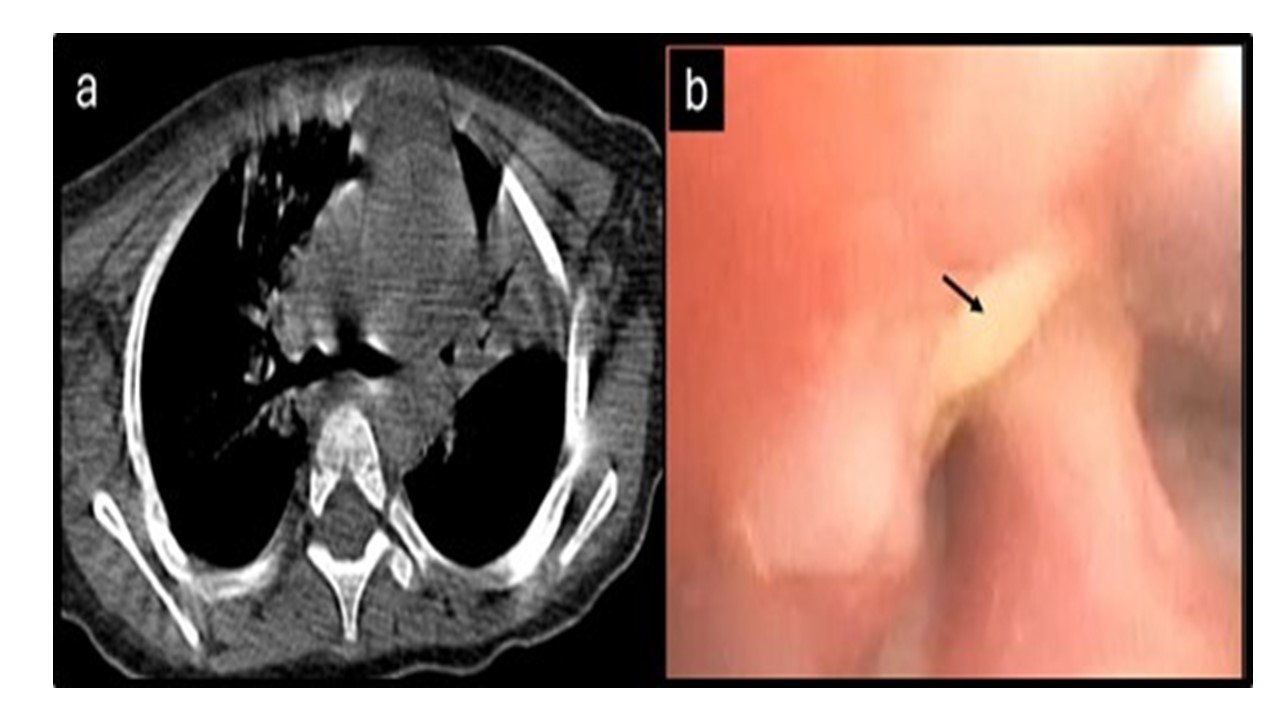

Multiple attempts to extract the FB with rigid and flexible forceps failed as the FB was impacted deep into the mucosa. In view of desaturation, he was intubated using a 3.0 mm uncuffed endotracheal tube to secure the airway. Following intubation, the patient maintained oxygenation for a while; however she developed sudden bradycardia followed by hypoxia leading to asystole, which required one cycle of cardiopulmonary resuscitation (CPR) to achieve return of spontaneous circulation. A repeated chest CT was done to assess the lung condition and FB, which showed displacement of the FB in the right bronchus intermedius with bilateral lower lobe consolidations (Figure 2A). Given the need for CPR due to airway obstruction, extracorporeal membrane oxygenation (ECMO) was initiated, and the infant was placed on veno-arterial extracorporeal life support (VA ECMO) to assist the interventional procedure for removal of the FB from the airways.

CT chest showing a foreign body in the right bronchus intermedius and flexible bronchoscopy confirming the foreign body at the same site

Figure 2. A - Computed tomography (CT) of the chest showing a foreign body in the right bronchus intermedius. B - Flexible bronchoscopy showing the foreign body (black arrow) it the right bronchus intermedius.